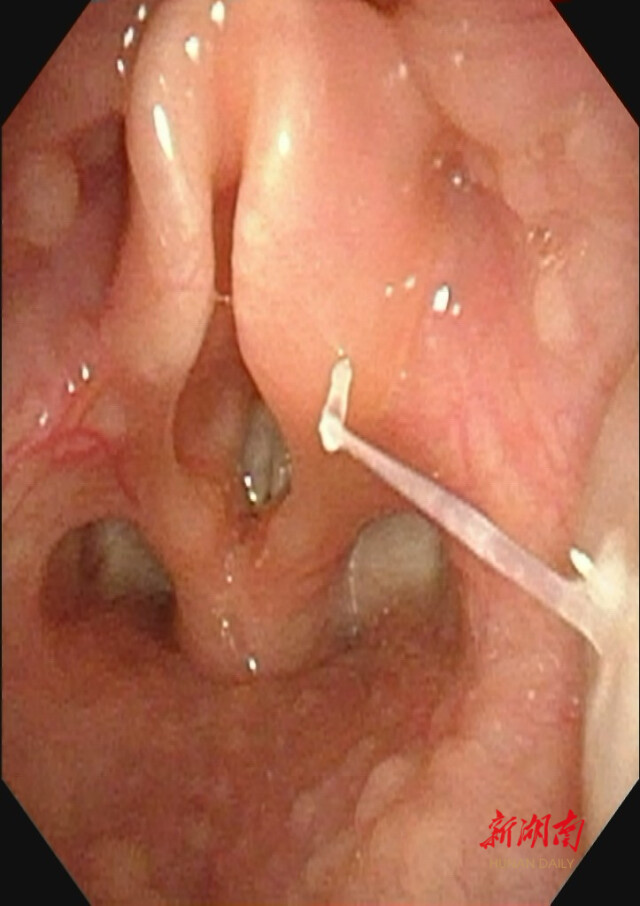

华声在线2月17日讯(全媒体记者 王铭俊 通讯员 马丹)近日,出生仅11个月的女婴琪琪在进食时突然出现呕吐及哭闹不适,随后不愿继续进食进水,妈妈怀疑在给琪琪做的辅食里有鱼刺没挑干净,担心琪琪被鱼刺卡住,赶紧带着孩子来到湖南省儿童医院耳鼻咽喉头颈外科就诊。医生根据家长描述的病情,高度怀疑咽部异物可能,为孩子进行了电子鼻咽喉镜检查,随后在琪琪的右侧扁桃体下极部使用耳鼻喉科专科器械成功取出一根近2厘米长的鱼刺。